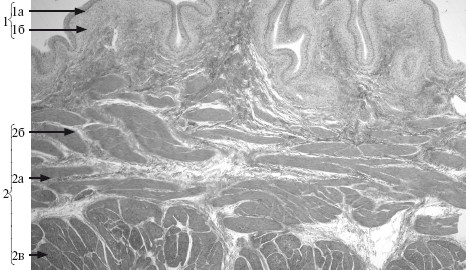

Рис. 17.2. Мочевой пузырь. х 14.

1 – ализистая оболочка: 1а – переходный эпителий, 1б – собственная пластинка; 2 – мышечная оболочка: 2а – внутренний продольный одой, 2б – средний циркулярный слой, 2в – наружный косой слой.